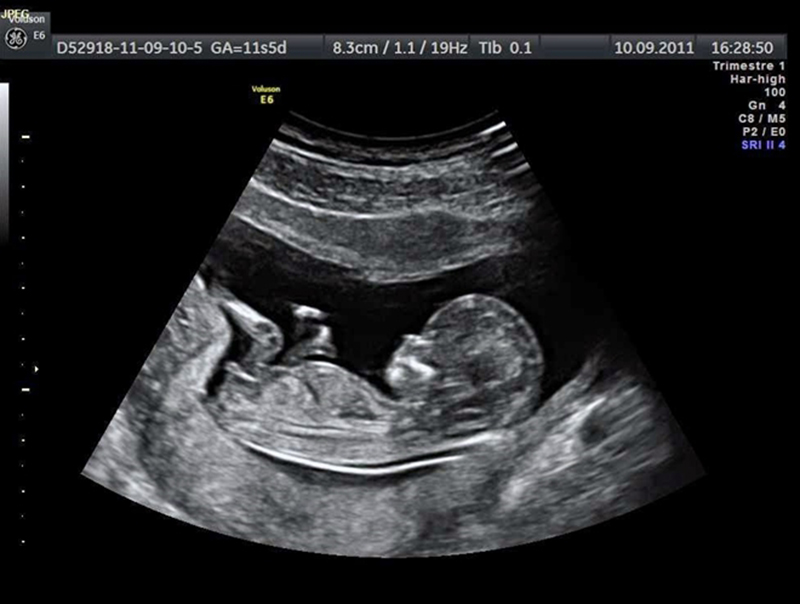

Hình ảnh siêu âm giúp chẩn đoán chính xác bệnh lý.